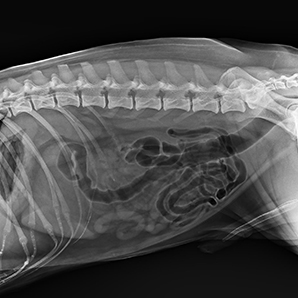

Get a high-quality instant image

Instant images on the tube head allow faster diagnoses and enable better communication with animal owners intuitively and clearly.